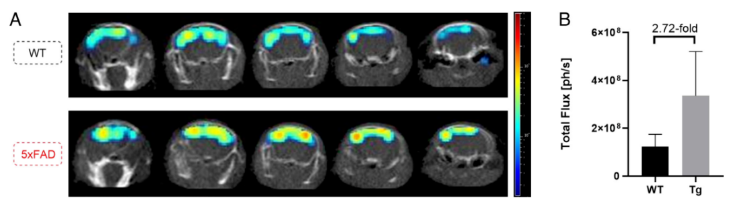

在小鼠的3D腦成像研究中,作者發(fā)現(xiàn)信號(hào)可達(dá)小鼠腦部深層0.5 cm處(圖4)。并且,對(duì)比野生型和AD小鼠不同位置的3D腦成像信號(hào)強(qiáng)度均有不同,差別可達(dá)2.72倍,相較于二維腦成像的信號(hào)差別(1.8倍)有所增加。所以,該方法不僅可以區(qū)分健康和AD小鼠,同時(shí)也提高了定量分析結(jié)果(圖5)。

圖5. 三維腦成像區(qū)分健康和疾病小鼠。圖片來源:PNAS